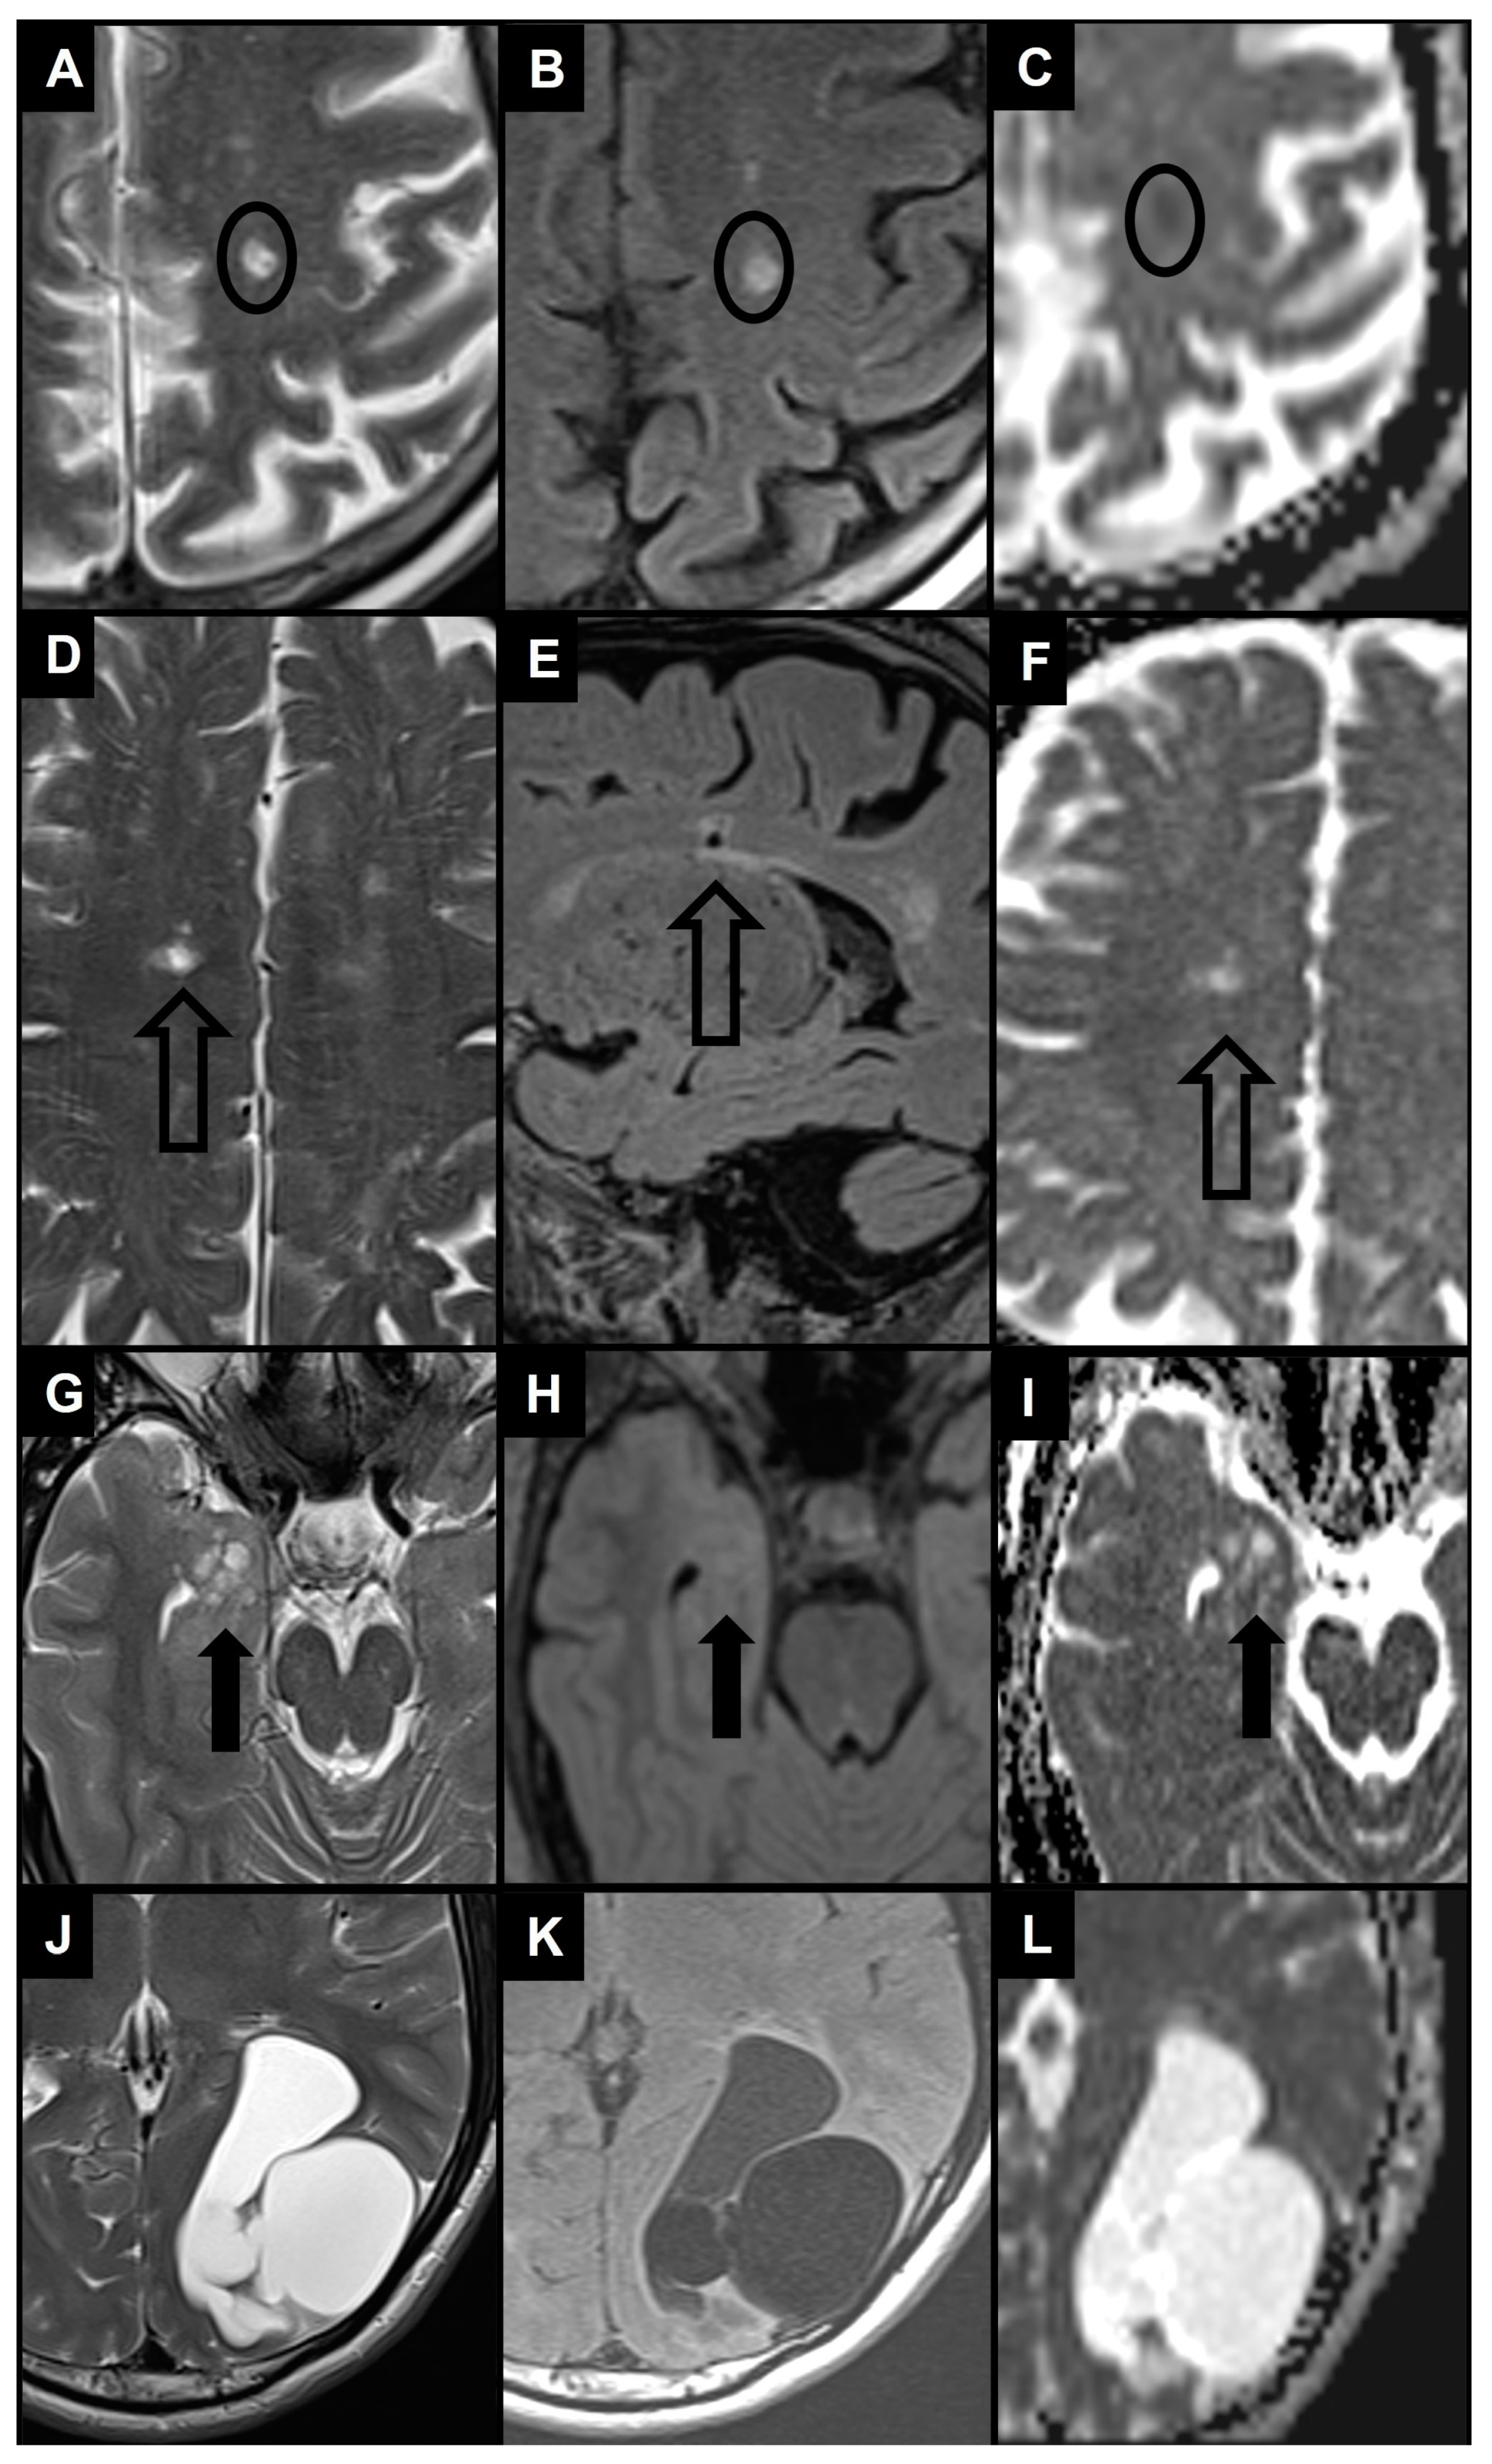

- Heier, L.A.; Bauer, C.J.; Schwartz, L.; Zimmerman, R.D.; Morgello, S.; Deck, M.D. Large Virchow-Robin Spaces: MR-Clinical Correlation. AJNR Am. J. Neuroradiol. 1989, 10, 929–936. [Google Scholar]

- Kwee, R.M.; Kwee, T.C. Virchow-Robin Spaces at MR Imaging. Radiogr. Rev. Publ. Radiol. Soc. N. Am. Inc. 2007, 27, 1071–1086. [Google Scholar] [CrossRef]

- Salzman, K.L.; Osborn, A.G.; House, P.; Jinkins, J.R.; Ditchfield, A.; Cooper, J.A.; Weller, R.O. Giant Tumefactive Perivascular Spaces. AJNR Am. J. Neuroradiol. 2005, 26, 298–305. [Google Scholar]

- Barisano, G. Neuroimaging Aspects and Clinical Significance of Giant Perivascular Spaces in the Brain. Precis. Cancer Med. 2022, 5, 31. [Google Scholar] [CrossRef]

- Rudie, J.D.; Rauschecker, A.M.; Nabavizadeh, S.A.; Mohan, S. Neuroimaging of Dilated Perivascular Spaces: From Benign and Pathologic Causes to Mimics. J. Neuroimaging Off. J. Am. Soc. Neuroimaging 2018, 28, 139–149. [Google Scholar] [CrossRef] [PubMed]

- Kwee, R.M.; Kwee, T.C. Tumefactive Virchow-Robin Spaces. Eur. J. Radiol. 2019, 111, 21–33. [Google Scholar] [CrossRef] [PubMed]

- Rawal, S.; Croul, S.E.; Willinsky, R.A.; Tymianski, M.; Krings, T. Subcortical Cystic Lesions within the Anterior Superior Temporal Gyrus: A Newly Recognized Characteristic Location for Dilated Perivascular Spaces. AJNR Am. J. Neuroradiol. 2014, 35, 317–322. [Google Scholar] [CrossRef]

- Lim, A.T.; Chandra, R.V.; Trost, N.M.; McKelvie, P.A.; Stuckey, S.L. Large Anterior Temporal Virchow-Robin Spaces: Unique MR Imaging Features. Neuroradiology 2015, 57, 491–499. [Google Scholar] [CrossRef] [PubMed]